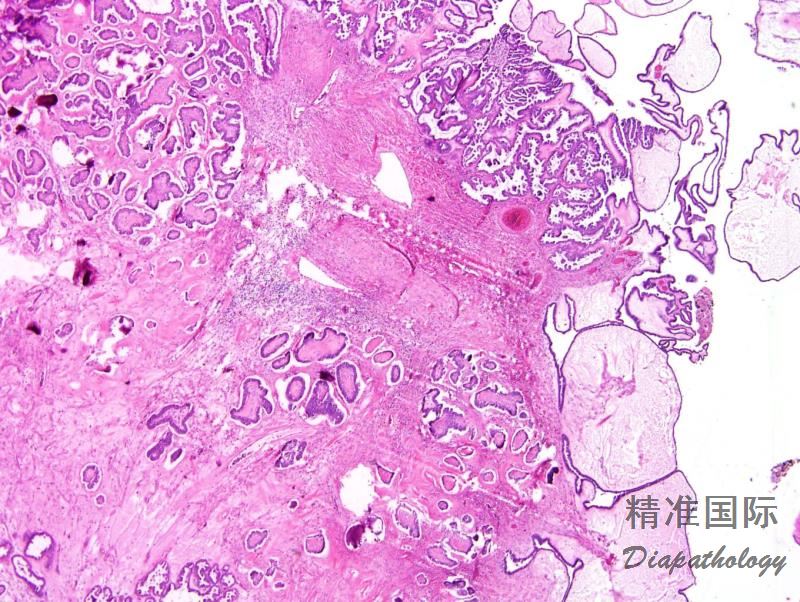

常累及双侧卵巢,呈细乳头生长方式;

特征性改变是各种类型的间质浸润,如单个细胞、不规则小细胞巢杂乱浸润间质;微乳头或大乳头周围围以无上皮衬覆的空隙;不同浸润方式可同时存在;

相当一部分低级别浸润性癌伴有浆液性交界性肿瘤/非典型增生性浆液性肿瘤;

砂粒体常见。